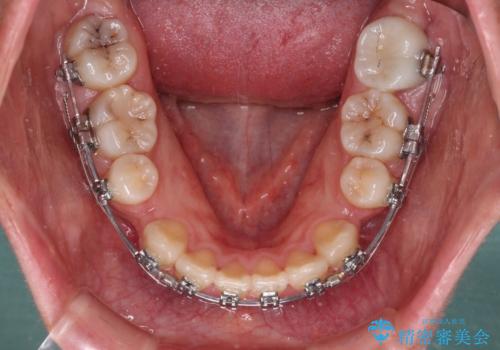

- メタルブラケット

- 2年4ヶ月

口元を積極的に引っ込めるために、上下左右の第一小臼歯を4本抜歯することとし、ワイヤー装置による矯正治療を行うこととしました。

上下前歯がくちばしのように突出していましたが、抜歯矯正により口元が引っ込み、唇が閉じやすくなり、鼻の下の膨れた感じも解消されました。